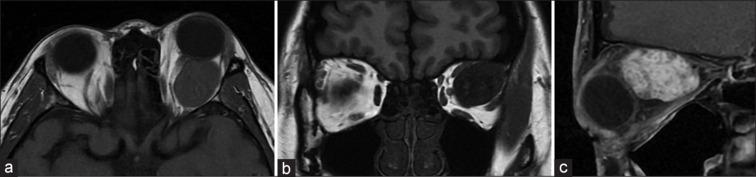

To propose a needle aspiration technique for the surgical removal of orbital cavernous hemangioma. In this retrospective case series, we enrolled 13 patients with orbital cavernous hemangioma, who underwent excisional surgery assisted with needle aspiration technique from June 2013 to April 2022. Preoperative symptoms, clinical examination, and imaging features were recorded. Surgical outcomes, including the improvement of visual acuity, proptosis, and ocular motility, were assessed. Postoperative complications were also reported. There were 11 female and two male patients, with a mean age of 50.2 ± 8.0 years (range: 38-61 years). The most common symptom was proptosis (12 cases, 92%), followed by blurred vision (6 cases, 46%). The diameter of the lesions was between 1.8 and 3.2 cm on preoperative imaging. The surgical approaches included sub-brow orbitotomy in 11 patients and the inferior transconjunctival approach in two cases. All the tumors were removed successfully after needle aspiration of 1-3 cc of intralesional blood to reduce the tumor size. Preoperative proptosis, blurred vision, and diplopia improved after the surgery in all cases. There were no serious complications or recurrence of orbital hemangioma. The study presented an effective application of the needle aspiration technique in the surgical management of orbital cavernous hemangioma. Such an innovative method can bring significant benefits, especially for those with large cavernous hemangioma within the deep orbital region.

提出一种用于手术切除眼眶海绵状血管瘤的针吸技术。在这项回顾性病例系列研究中,我们纳入了 2013 年 6 月至 2022 年 4 月期间接受针吸辅助切除术治疗的 13 例眼眶海绵状血管瘤患者。记录了术前症状、临床检查和影像学特征。评估了手术结果,包括视力、眼球突出度和眼球运动的改善。还报告了术后并发症。患者中 11 例为女性,2 例为男性,平均年龄为 50.2 ± 8.0 岁(范围:38-61 岁)。最常见的症状是眼球突出(12 例,92%),其次是视力模糊(6 例,46%)。术前影像学上病变直径为 1.8-3.2cm。手术入路包括 11 例经眉弓眶切开术和 2 例经下经结膜入路。所有肿瘤在经皮抽吸 1-3cc 瘤内血液以缩小肿瘤体积后均成功切除。所有患者的术前眼球突出度、视力模糊和复视在手术后均得到改善。无严重并发症或眼眶血管瘤复发。本研究提出了一种在眼眶海绵状血管瘤的外科治疗中应用针吸技术的有效方法。这种创新的方法特别适用于深部眼眶内大的海绵状血管瘤患者。